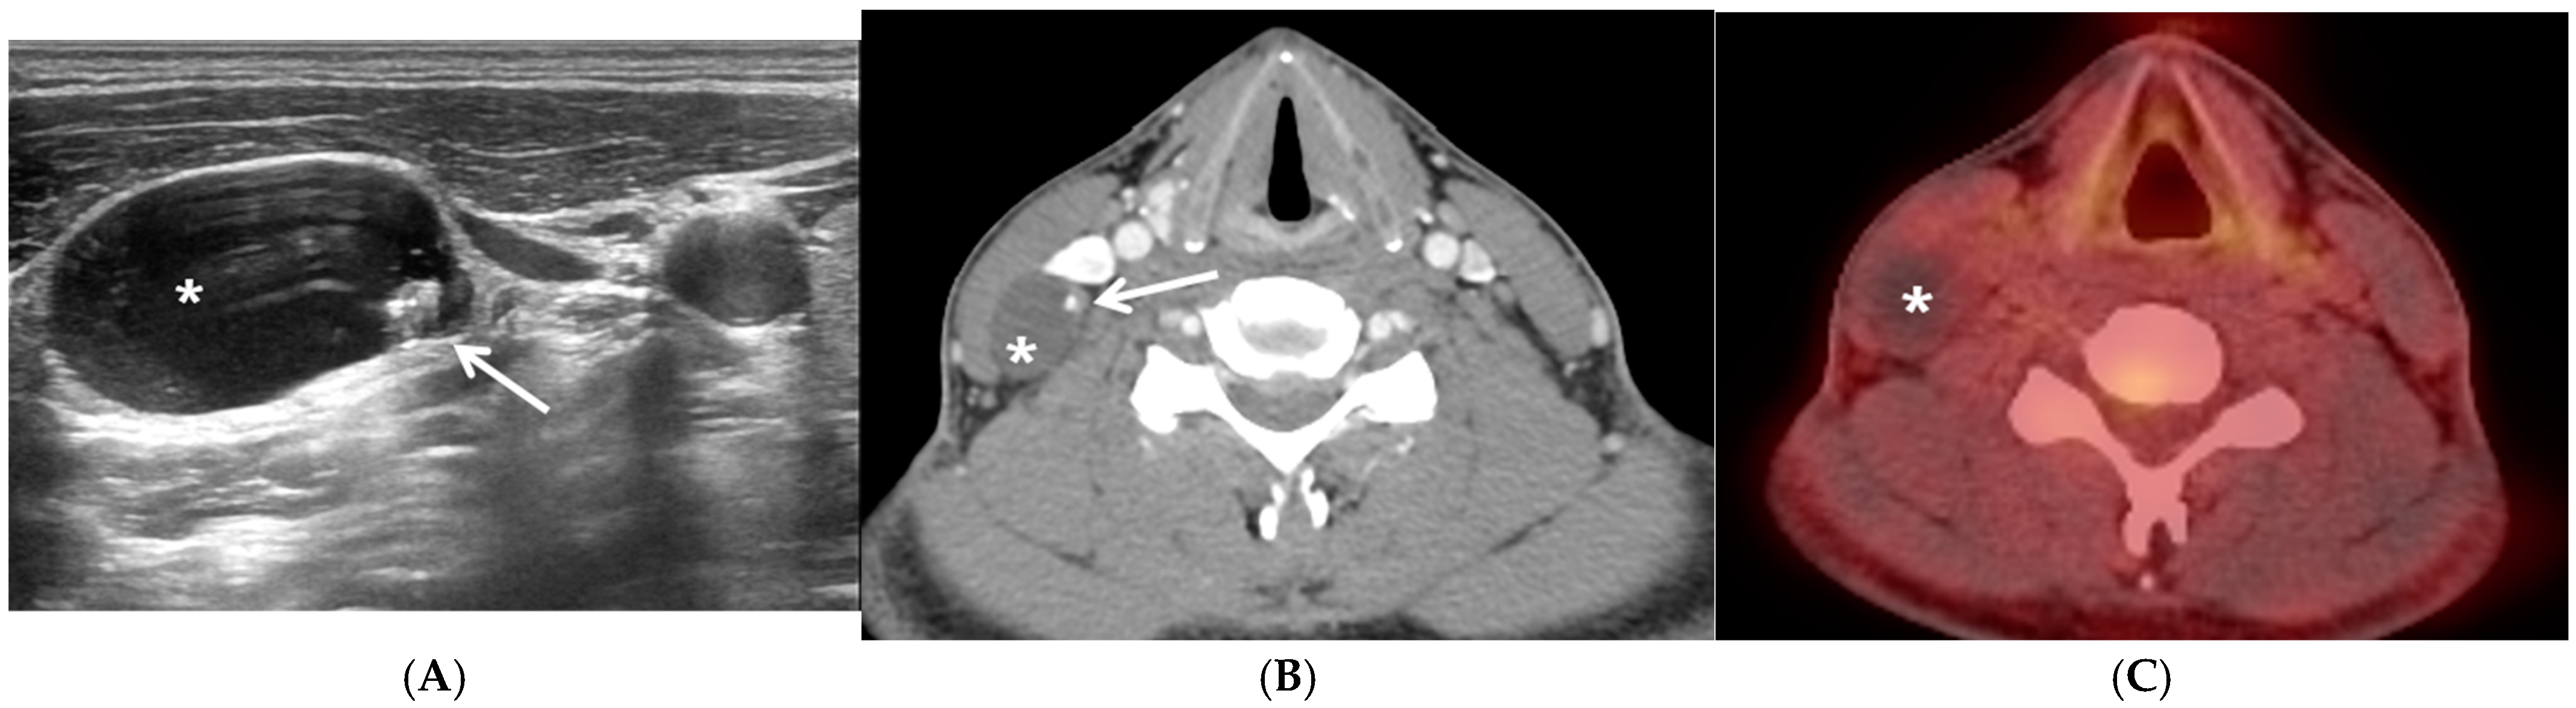

A 31-year-old man presented with a soft, painless, non-tender mass in the right lateral neck that had persisted for 1 month. US and contrast-enhanced CT revealed a cystic mass on the right neck at level III (Figure 1A,B). No abnormal lesions were observed in the thyroid on US or CT. The FNAB result was consistent with PTC, and the increased washout Tg levels (>500 ng/mL) facilitated diagnosis. F-18 FDG PET/CT was performed to exclude other possible malignancies that could metastasize to the lateral neck. The mass exhibited no obvious F-18 FDG uptake or other hypermetabolic lesions on F-18 FDG PET/CT (Figure 1C). The preoperative diagnosis was a presumed metastatic thyroid carcinoma in the lateral neck. After excising the cystic mass, the PTC was identified using frozen section analysis. The patient underwent total thyroidectomy, along with a comprehensive neck dissection of the central (both level VI) and lateral neck compartments (right, levels II–V). The patient was managed with levothyroxine replacement therapy.

Figure 1.

Representative case of papillary thyroid carcinoma in solitary lateral neck cystic mass without identifiable primary carcinoma within the thyroid. Preoperative ultrasonography (US) (A) and computed tomography (CT) (B) showing a 25 mm × 16 mm-sized lobular, well-defined, cystic mass (asterisk) containing a solid and hyperechoic lesion with punctate calcification (white arrow) in the right neck at level III (A,B) without other enlarged lymph nodes on either side of the neck and normal findings in the thyroid. The cystic lateral neck mass in the right neck exhibited no obvious F-18 fluorodeoxyglucose (FDG) uptake or any other suspicious F-18 FDG-avid lesions documented on positron emission tomography/CT (PET/CT) (C).